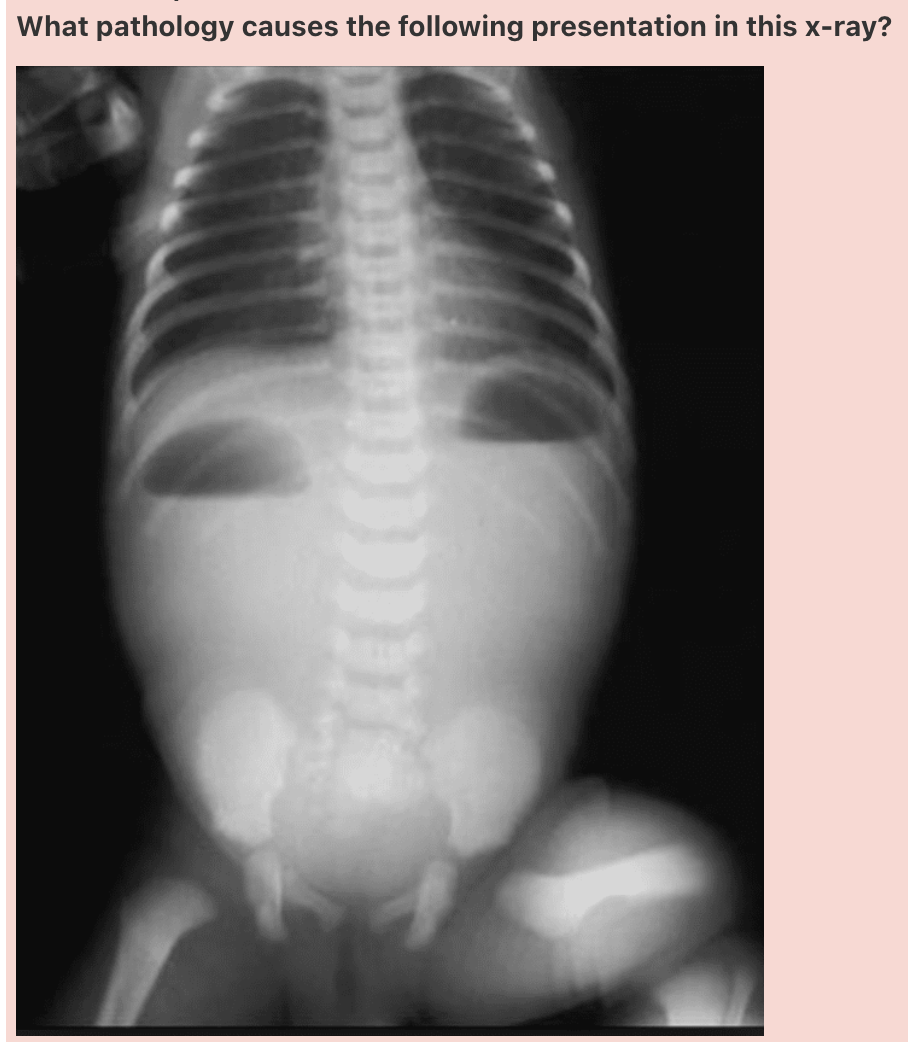

Answer: Hirschsprung’s Disease

How well did you know this?